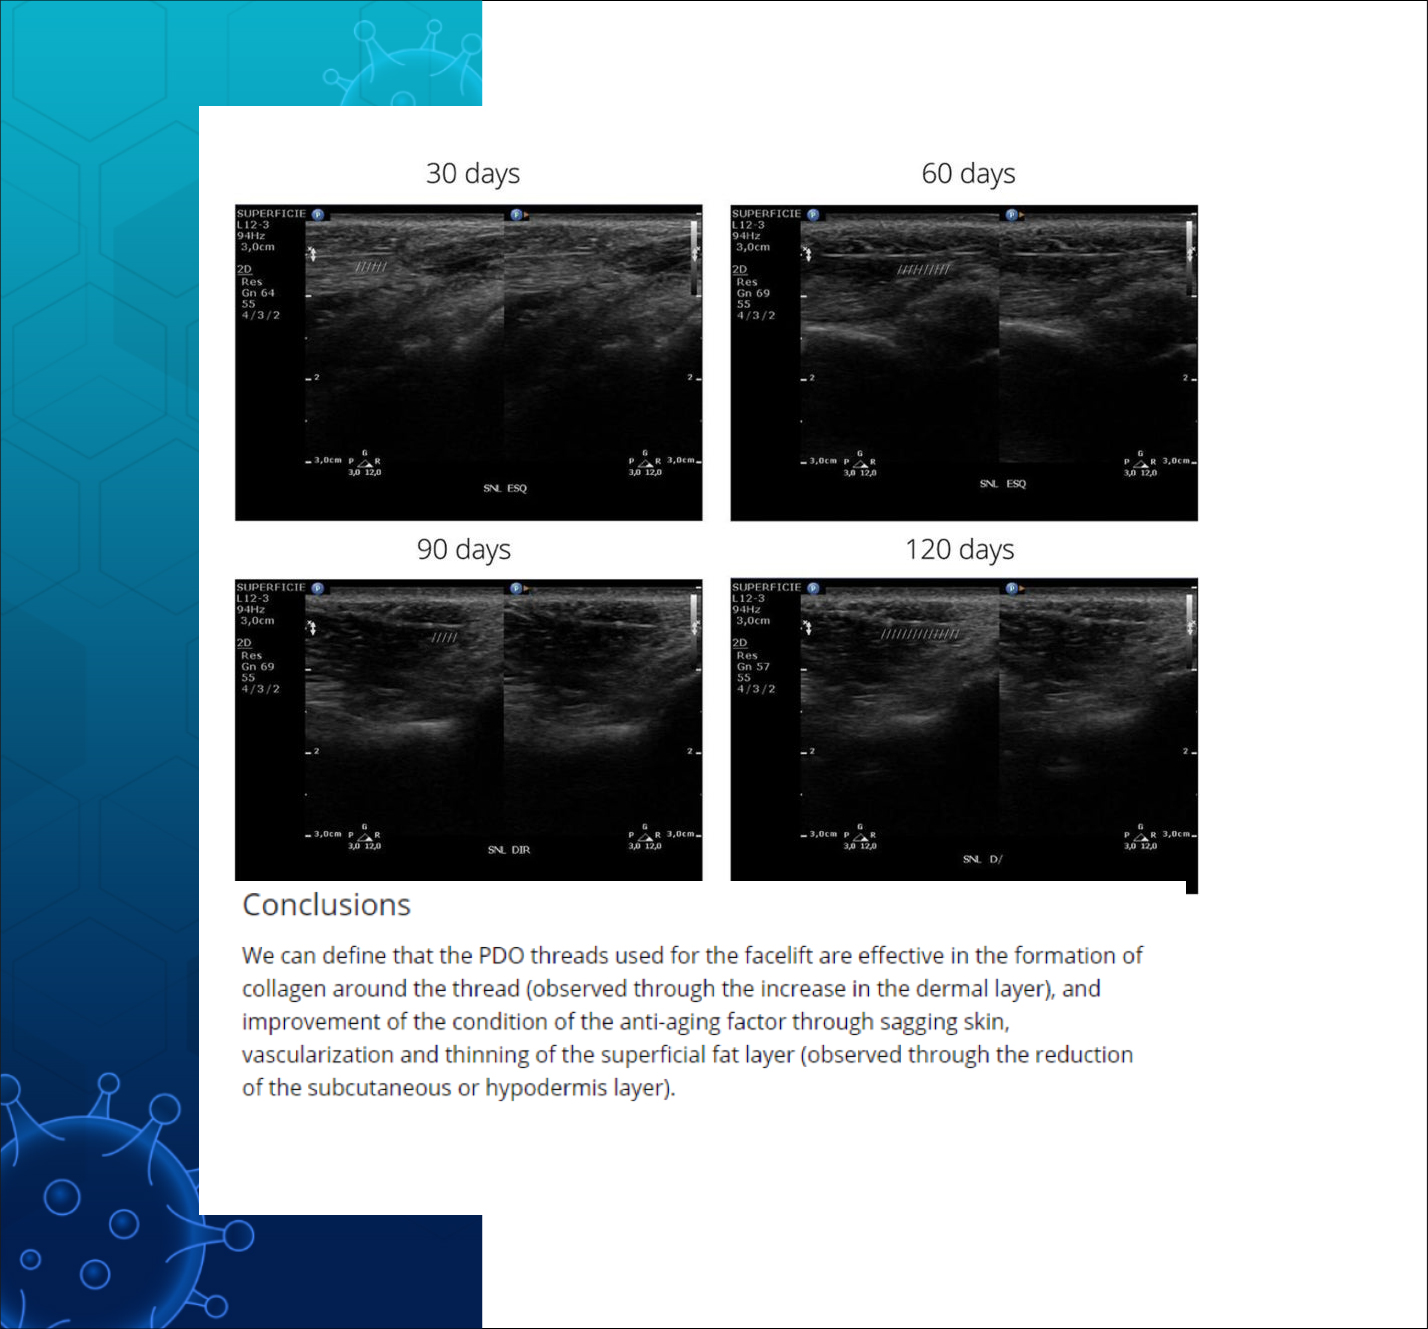

Conclusions

PDO실진피층의 두께는 증가시키고

(피부 탄력 증가)

혈관 형성을 촉진하며

콜라겐 형성을 촉진하고

피하지방층의 감소도 유발하는것으로

실험 대상 모두에게서

초음파 검사를 통해 관찰 되었다.

Effect of pdo facelift threads on facial skin tissues: An ultrasonographic

analysis - Lots - 2023 - Journal of Cosmetic Dermatology - Wiley Online

Library - https://onlinelibrary.wiley.com/doi/full/10.1111/jocd.15761